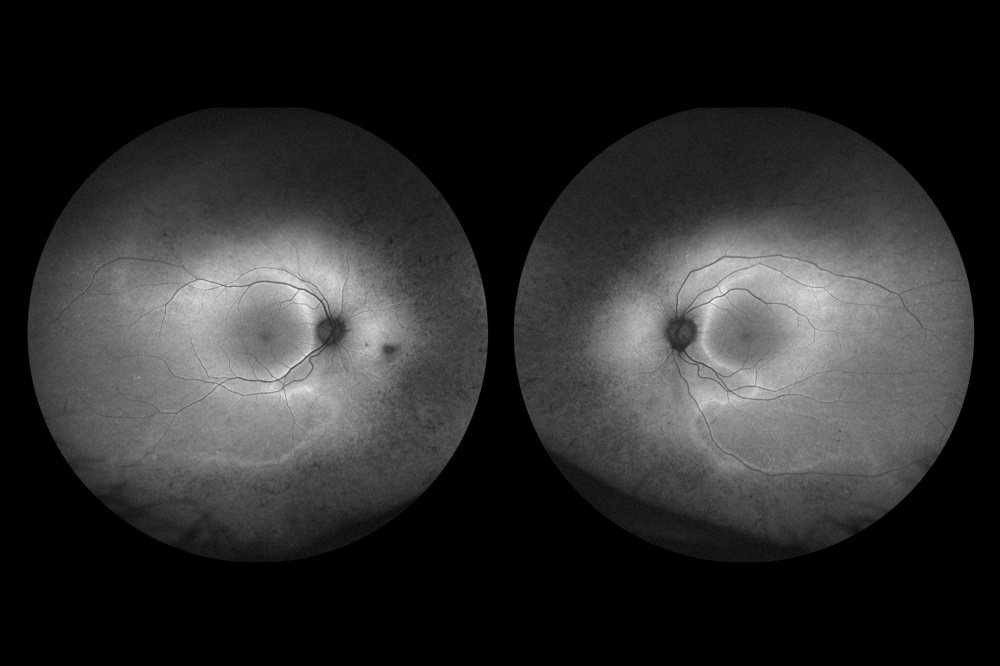

Título: Flower power: hemorragia na camada de fibras de Henle no síndrome de Terson

Descrição: Hemorragia na camada de fibras de Henle no síndrome de Terson. Retinografia demonstrando múltiplas hemorragias intraretinianas petalóides a irradiar a partir da fóvea, bilateralmente. A morfologia floral é melhor evidenciada na autofluorescência. A tomografia de coerência óptica revela depósito hiperrefletivo foveal e no trajeto oblíquo delineado pelas fibras de Henle, correspondente às hemorragias radiárias.